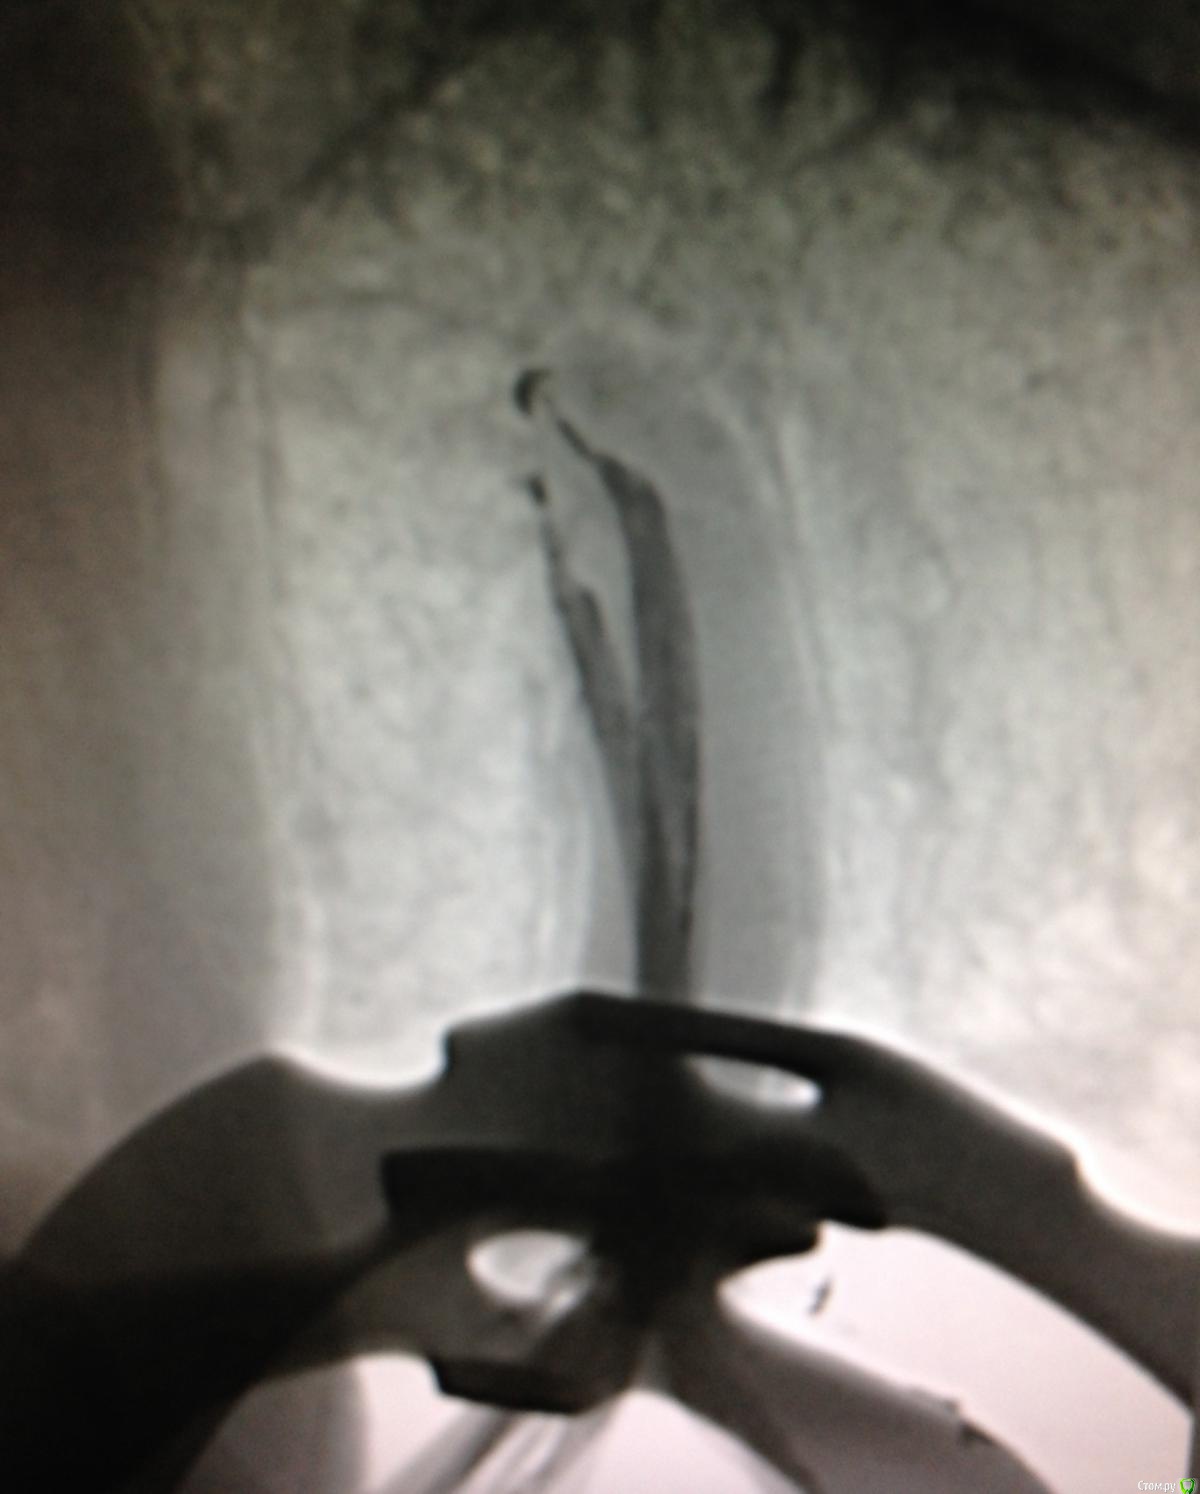

SSTi Опубликовано 21 января, 2015 Автор Поделиться Опубликовано 21 января, 2015 Легкий и приятный кейс. 46. Витальное эндо. Медиальные 35.04, дистальные 40.04. Дистальных 2. В конце инструментации ушла перегородка и они объединились в 1 протяженный щелевидный канал. Латералка. 7 Ссылка на комментарий

SSTi Опубликовано 4 февраля, 2015 Автор Поделиться Опубликовано 4 февраля, 2015 45. Многострадальный. 1- изоляция. Преп. Извлечения штифта. 40.04-70.02. Гх-эдта-гх уз - эдта - кальций. ЦемилайтПериостотомия2- изоляция- преп- эдта- гх уз - аспирация - перекись - хг. ОбтурацияЛатералка с модификацией) 4 1 Ссылка на комментарий